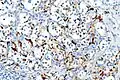

On microscopic inspection, the tumor cells are readily recognized. Individual tumor cells are polygonal to oval and are arranged in distinctive cell balls, called Zellballen.[8] These cell balls are separated by fibrovascular stroma and surrounded by sustentacular cells.

With immunohistochemistry, the chief cells located in the cell balls are positive for chromogranin, synaptophysin, neuron specific enolase, serotonin, neurofilament and Neural cell adhesion molecule; they are S-100 protein negative. The sustentacular cells are S-100 positive and focally positive for glial fibrillary acidic protein. By histochemistry, the paraganglioma cells are argyrophilic, periodic acid Schiff negative, mucicarmine negative, and argentaffin negative.

S100 immunostain highlighting the sustentacular cells in a paraganglioma